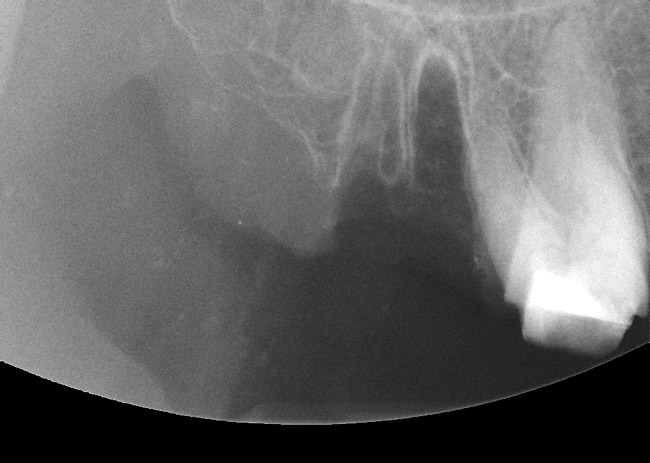

Figure 1  Occlusal view after extraction of tooth No. 27 using Piezosurgery<sup>®</sup> (Piezosurgery Inc, www.piezosurgery.com) and thin-bladed elevators.

Figure 1

Figure 15  After extraction, the outline of the socket is  visualized radiographically.

Figure 15